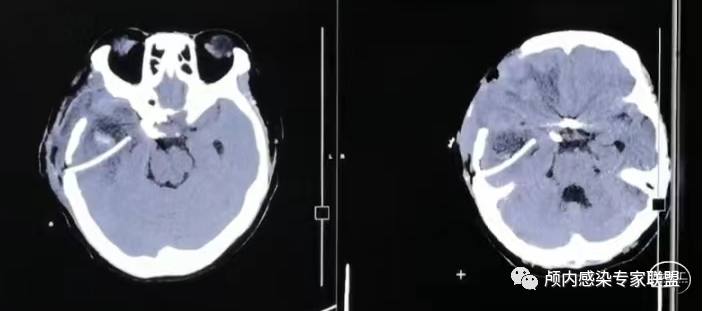

颞角孤立

急诊手术为患者做了孤立颞角的体外引流,颞角脑脊液培养回报:金黄色葡萄球菌,按照术区的方案给予抗感染治疗,一周后颞角细菌培养转阴。

颞角引流术后